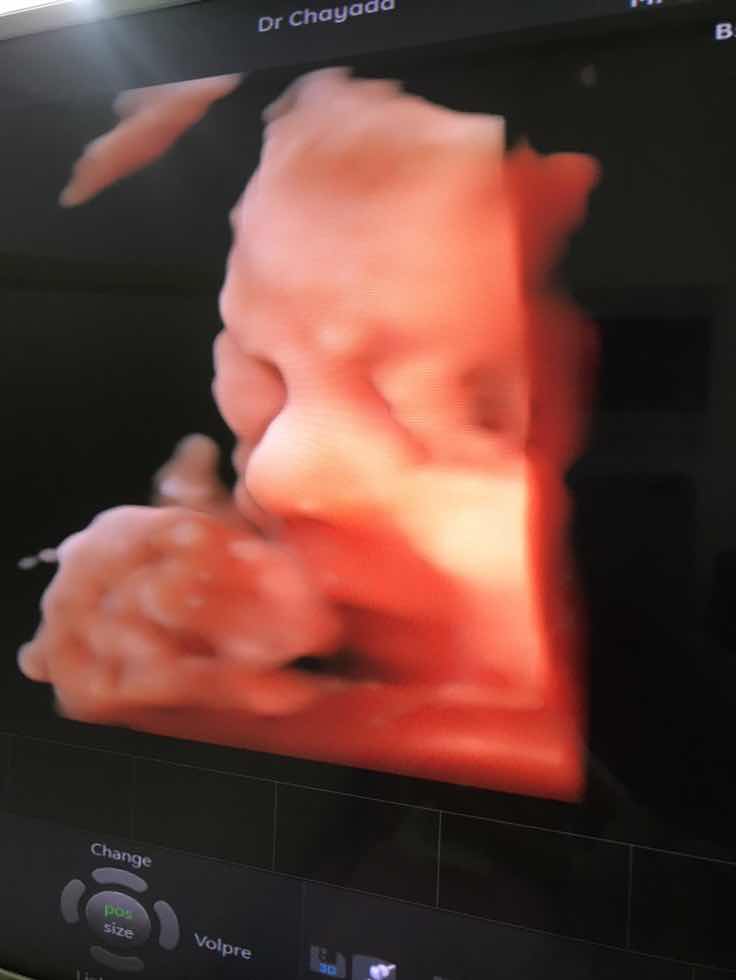

บ้านนี้ชอบเอาเท้าบัง มือบังค่ะ

เอามือบังเหมือนกันค่ะ😆😆